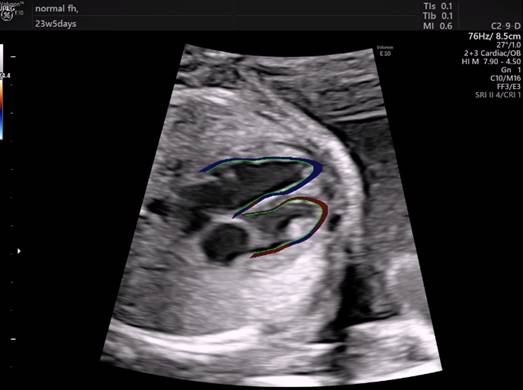

This new tool – called fetalHQ – runs on GE Healthcare’s Voluson ultrasound systems and is the first tool to simultaneously examine the size, shape and function of the fetal heart.

“This is an incredible step forward in examining the fetal heart. Previously, we had various tools that looked at specific sites of the heart – but nothing that examined the entire chamber,” DeVore said. “On top of this, the heart had to be in a specific position – at 12 or six o’clock on the screen to get the proper measurements. And this all required an advanced level of diagnostic skills to learn the techniques.”